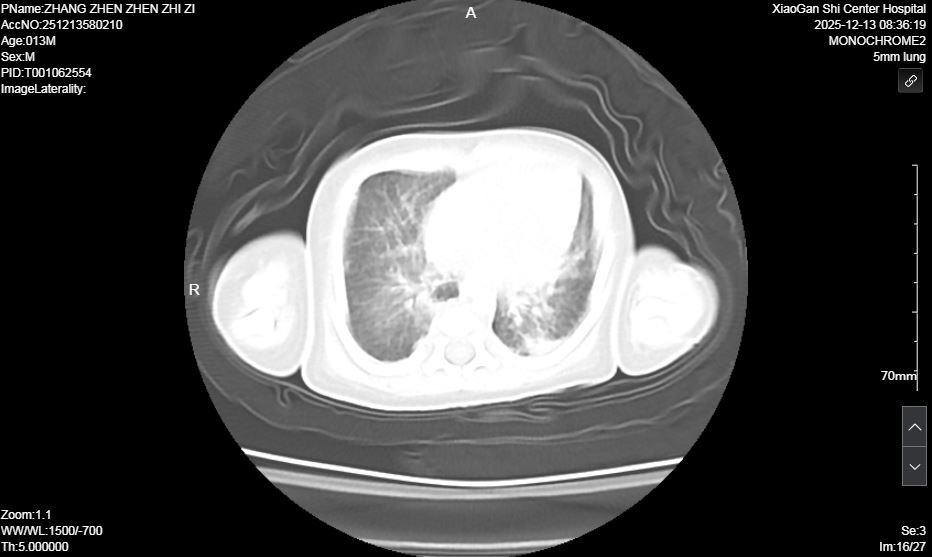

術前肺部超聲及CT均提示雙肺實變明顯

面對挑戰(zhàn),新生兒科迅速啟動多學科會診(MDT),聯(lián)合呼吸內科、兒童呼吸科、中心試驗室等科室專家深入討論。在充分與家長溝通并取得同意后,醫(yī)療團隊成功為患兒實施了本市首例新生兒纖維支氣管鏡和肺泡灌洗術,同時取灌洗液進行 NGS檢查、明確病原學診斷,團隊快速調整個性化診療方案,精準調控參數(shù)、嚴密監(jiān)測病情,穩(wěn)步推進階梯式撤機脫氧,全力攻克救治難關。